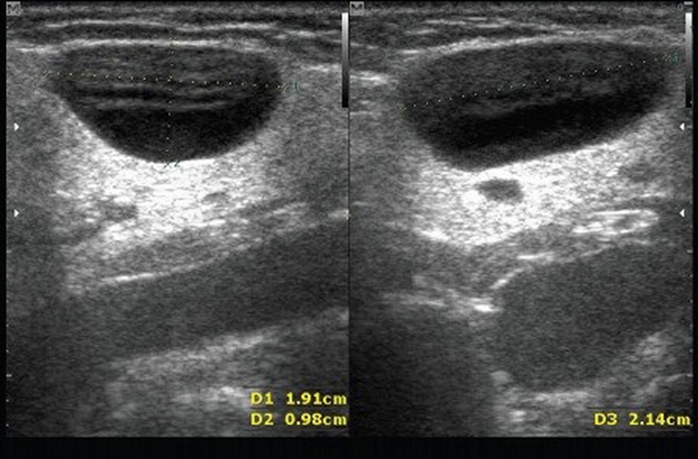

Эхографически кисты могут быть не только классически анэхогенными, но и гипоэхогенными (в зависимости от вязкости содержимого), имитируя солидные образования.

Рис. 1. Эхографическая визуализация кисты СЖ, В-режим, продольное (справа) и поперечное (слева) сканирование [1]